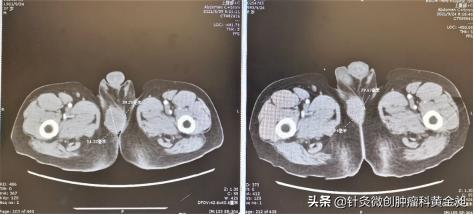

会阴区肿物5.1cm*3.9cm→3.9cm*2.9cm(左: 6月29日;右:9月24日)